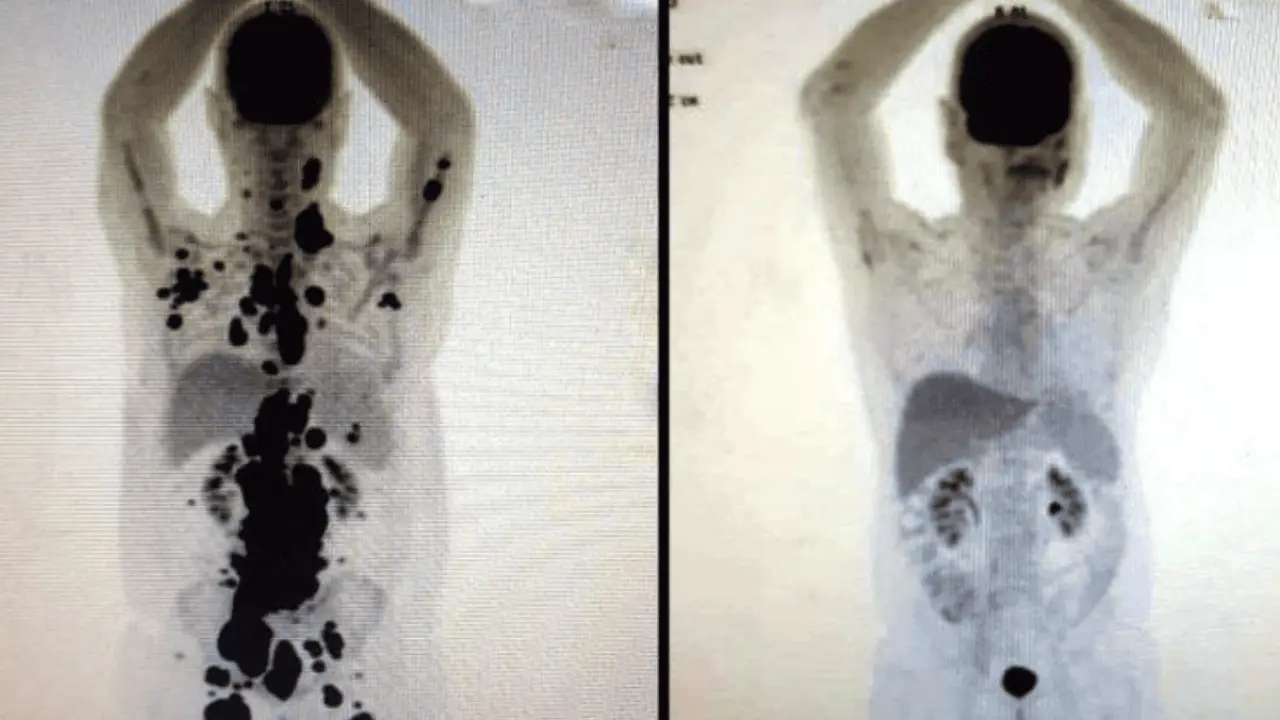

Paulo Peregrino, un paciente brasileño de 61 años, alcanzó la remisión total de un linfoma metastásico en apenas 30 días. El impactante resultado ocurrió tras someterse a la avanzada terapia de células CAR-T.

Las imágenes del "antes y después" se han vuelto virales por la rapidez de la recuperación. Lo que la medicina tradicional no logró en un lustro, esta inmunoterapia lo consiguió en solo cuatro semanas.

Paulo Peregrino calificó su curación como un "milagro de la ciencia" tras años de sufrimiento y trasplantes fallidos. Su caso se suma a los éxitos registrados desde que estas terapias fueron aprobadas en el año 2017.